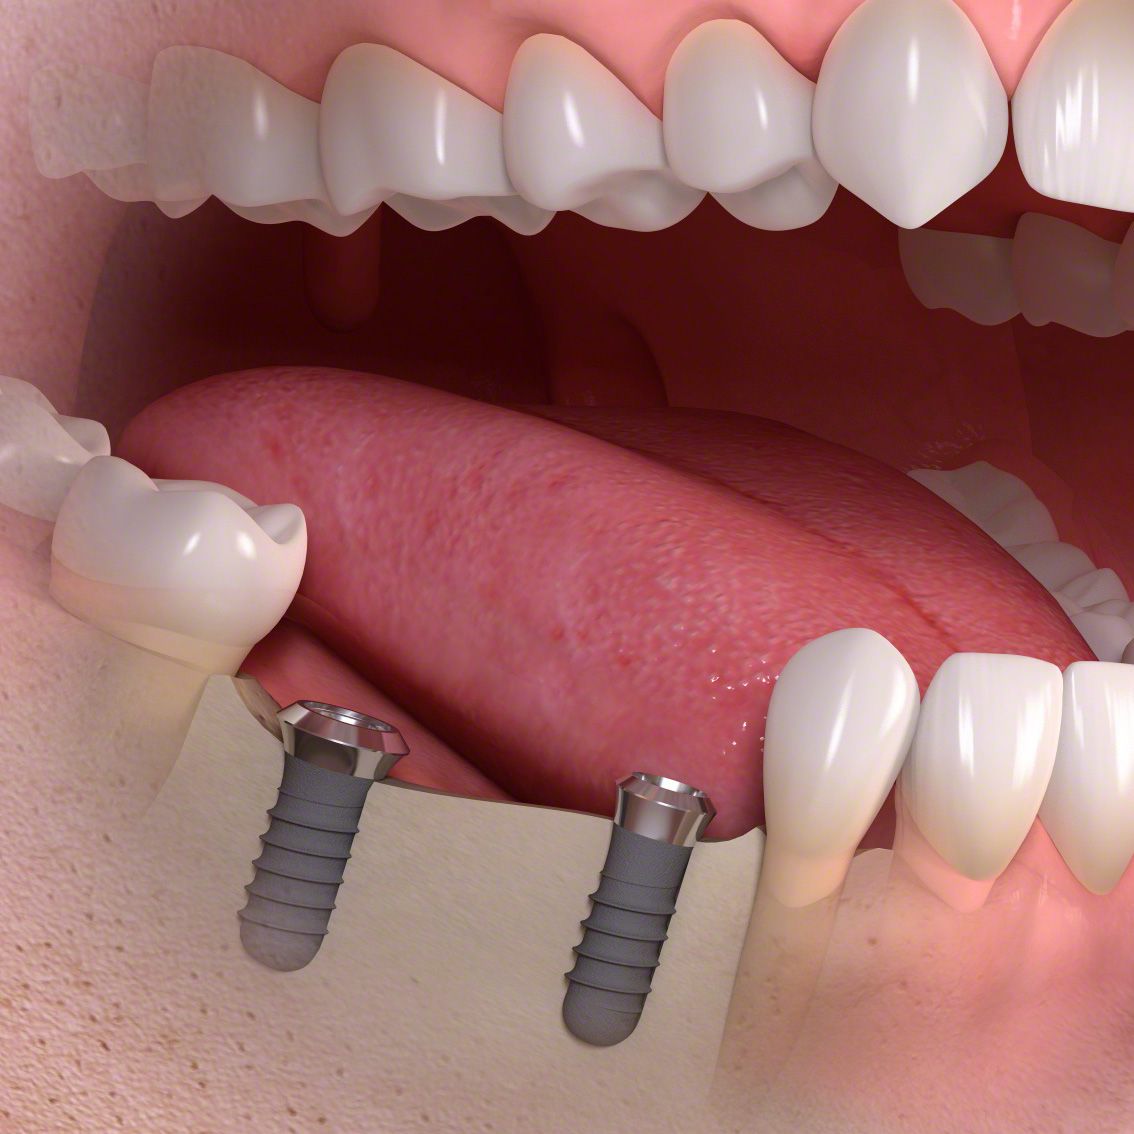

Die entstandene Lücke kann mit einer künstlichen Zahnwurzel, d.h. mit einem Implantat geschlossen werden. Implantate, meist aus Titan oder Keramik, werden dabei in einem kleinen chirurgischen Eingriff in den Kieferknochen eingesetzt. Nach dem Einheilen tragen sie später den eigentlichen Zahnersatz (Kronen, Brücken, Prothesen).